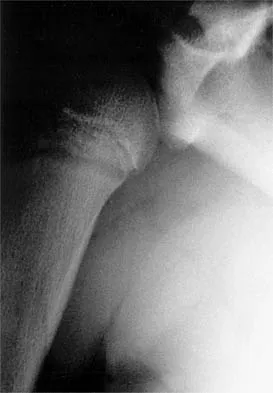

A paraplegic 32-year-old man was pulling himself up in bed by grasping the headboard rails when he felt a pop and immediate pain. A radiograph and CT scan are shown in Figures 2a and 2b. Based on these findings, management should consist of

Explanation

The coracoid process is an essential component of the superior shoulder suspensory complex and must be maintained. Open reduction and internal fixation is recommended if the fragment is large and displaced more than 1 cm. Froimson AI: Fracture of the coracoid process of the scapula. J Bone Joint Surg Am 1978;60:710-711.